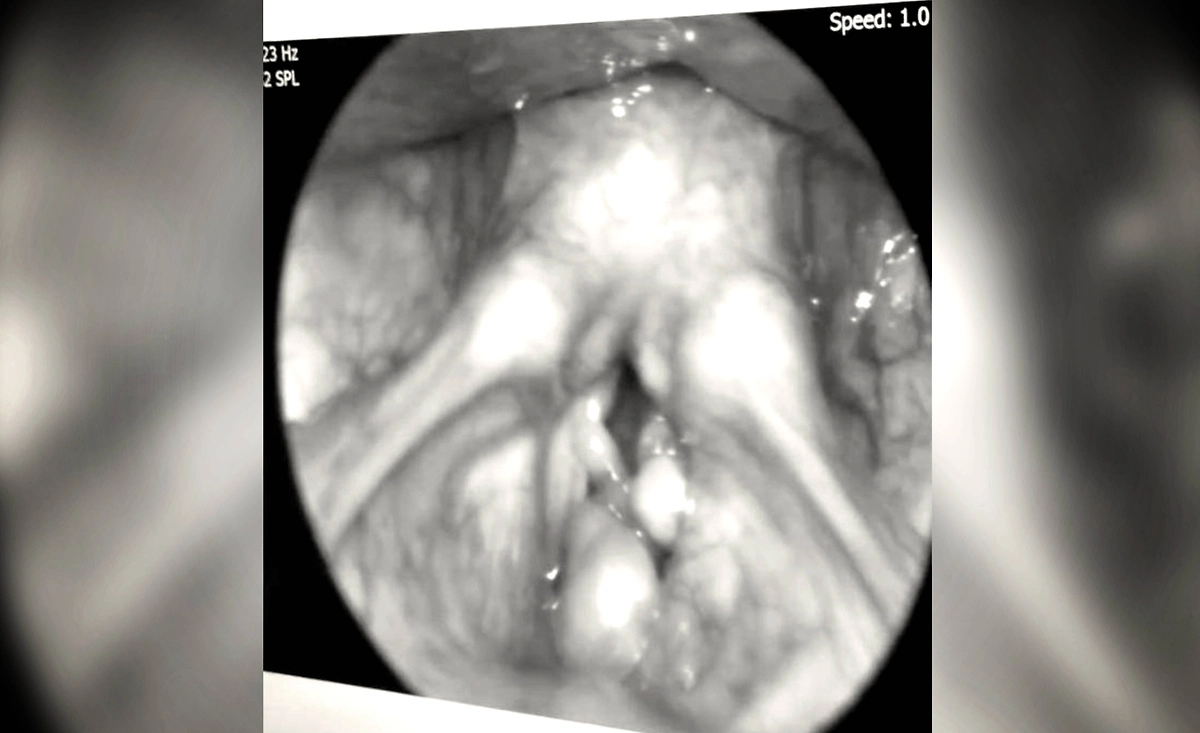

Москвич «заработал» опухоль из-за сигарет. Фото © Telegram / Baza

Три года мужчина устраивал над собой «эксперименты», чередуя вейпы и сигареты, а затем перешёл на системы нагревания табака и выкуривал по 5–10 стиков в день. Недавно он почувствовал, что голос начал сипеть, стали ощущаться боли, а также появились трудности с речью. Мужчина пошёл к врачам. В больнице сразу увидели крупную опухоль в гортани.